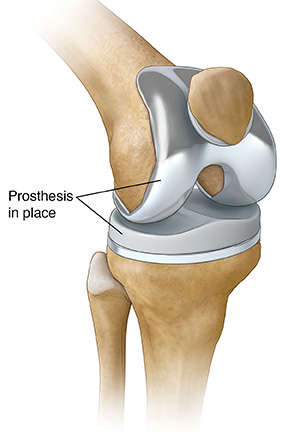

Next was a total knee replacement. This was probably the messiest. I had a pretty good view and got to see most of the cutting. The pounding in of the components is pretty traumatic. I can see why there is so much pain after a total knee. They used a series of reamers to get the hole deep and wide enough, again the rep talked the tech through exactly what to do. I saw the back of the patella that was removed and they let me play with the cement putty they use. It's heat activated and got very hot as it hardened in my hand.